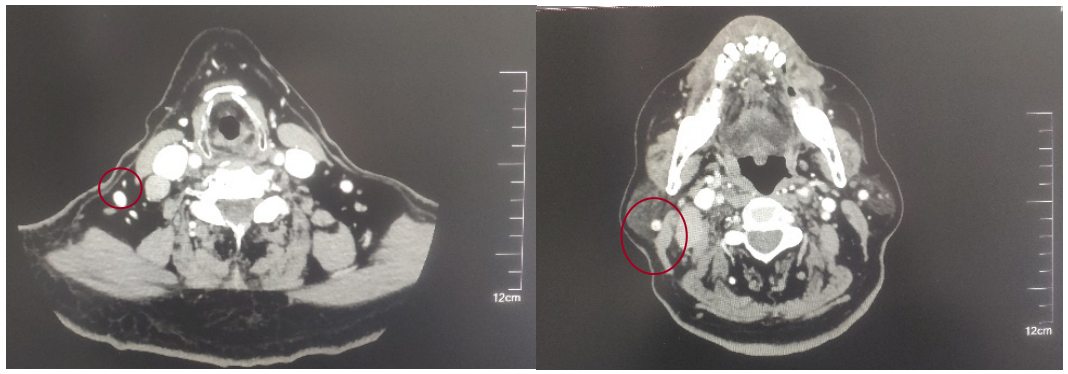

2022-05-05鼻咽部增强CT示:鼻咽CA并左侧翼腭弓、海绵窦受侵,伴邻近蝶窦、左侧筛窦、枕骨斜坡、左侧框下裂骨质破坏;右侧颈部多发肿大淋巴结(最大2.4×1.4cm),考虑转移;2.双侧梨状窝闭塞。

修正诊断:鼻咽癌T3N1M0,Ⅲ期。

2022-08-05(放疗近结束)复查MR,疗效评价:CR。鼻咽部肿物及咽后转移淋巴结颈部转移淋巴结均达到CR。